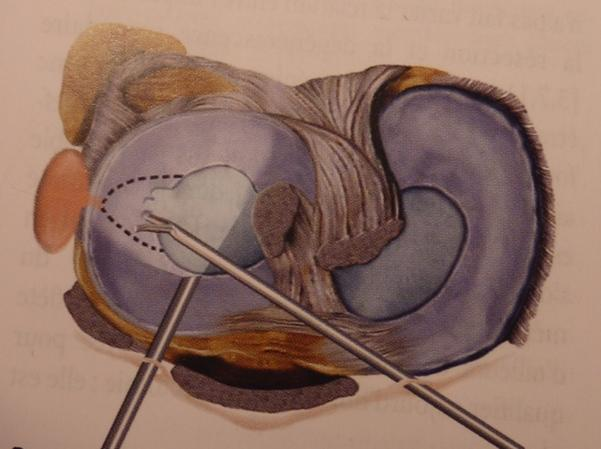

- Les lésions isolées (sur genou stable), siègent le plus souvent sur le bord libre du ménisque. Il s'agit de fissures verticales, radiaires, qui ne cicatrisent pas et qui peuvent détacher un fragment plus ou moins étendu (languette, anse de seau), source de blocage. Ces lésions doivent être réséquées par méniscectomie partielle.

Figure 2 : résection à l'aide d'une pince coupante d’une lésion en anse de seau du ménisque interne en vue de haut et en vue arthroscopique

Par 2 mini incisions de chaque côté du tendon rotulien, on introduit dans l'articulation un arthroscope et des pinces emporte pièces appelées pinces basket, qui permettent une résection économique de la lésion. En fonction de l’importance de la lésion, la méniscectomie peut être partielle ou étendue, segmentaire ou sur plusieurs segments (Figure 7).